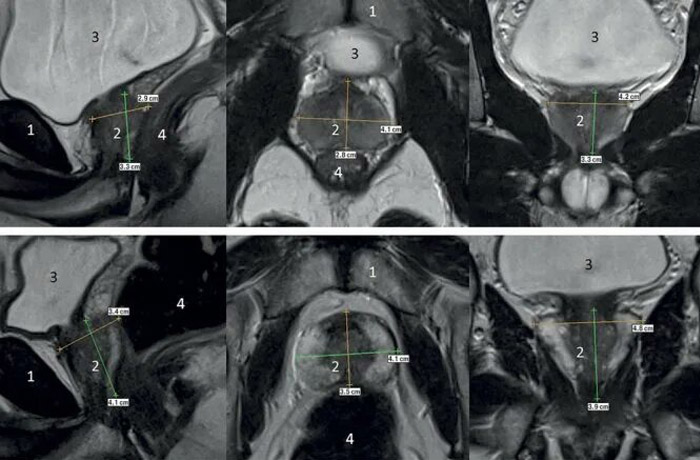

МРТ предстательной железы — современный метод диагностики, предоставляющий данные о состоянии простаты в формате трехмерного изображения для получения наиболее точных данных о клинической картине.